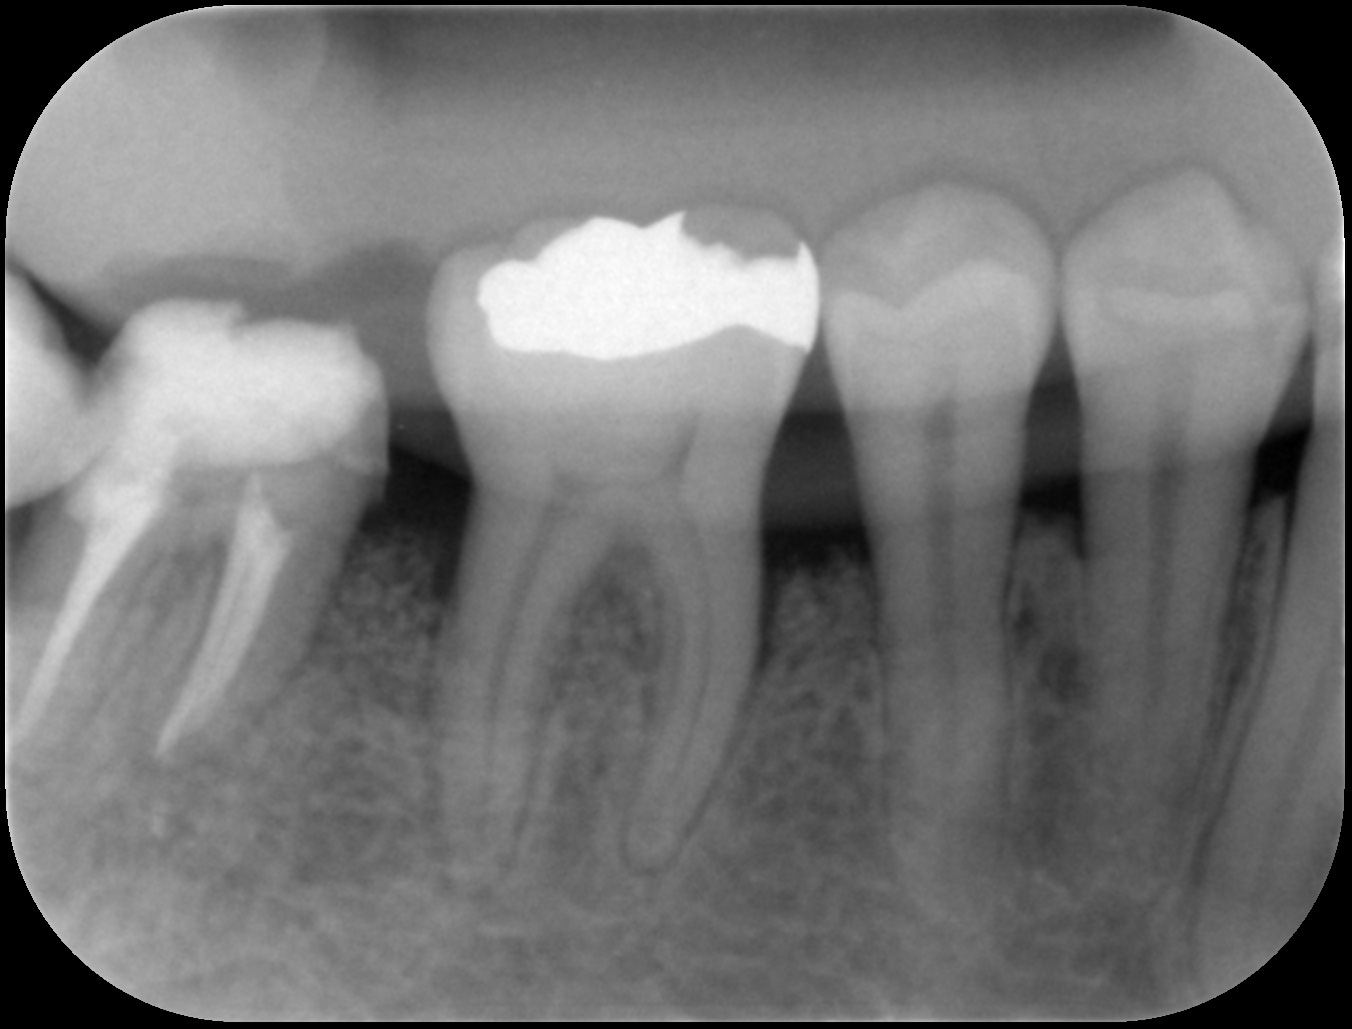

初診時

歯周基本治療後

歯周組織再生療法後6ヶ月

| 主訴 | 他院にて歯周病と診断され、抜歯するしかないと言われたが年齢的(初診時30代)に抜歯はしたくない。 歯周病の専門医に相談した方がいいと言われ当院を受診。 |

|---|---|

| 治療内容 | 精密検査の結果、歯周ポケット(歯と歯茎の間の溝)4mm以上の部位が全体の67%、最大11mmの歯周ポケットを認めた。*歯周ポケットの正常値は3mm以下。 またエックス線画像からは奥歯を中心に歯槽骨(歯を支える骨)の著しい吸収を認めた。 ブラッシング指導、歯肉縁上歯石の除去、歯肉縁下歯石の除去、根管治療を行った後、再評価検査を行った結果、全顎的に歯周外科治療が必要であったため歯周組織再生療法を行った。 |

| 治療期間 | 9ヶ月 歯周基本治療(2ヶ月) 歯周外科治療、歯周組織再生療法(2ヶ月) 歯周組織再生療法後は6ヶ月経過を確認しメインテナンスへ |

| 費用 | 歯周組織再生療法(サイトカイン+骨補填剤の併用療法) 165,000(1部位につき) |

| リスク・副作用 | サイトカインと骨補填剤を併用した歯周組織再生療法では術後の腫れや痛みを生じる場合があります。 歯周組織(特に歯槽骨)の再生が認められた後も定期的なメインテナンスやご自身でもブラッシングが大切です。それを怠ると再発や悪化につながりますのでご注意ください。 *当院ではブラッシング指導を徹底し、ご自身できちんと口腔内環境を管理できるようご協力いただいております。ブラッシング状況が改善されない場合は歯周外科治療へ進まないこともありますのでご理解ください。 |